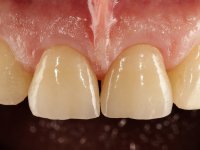

The suggested treatment consisted of two feldspathic ceramic veneers, with frontal insertion and incisal coverage.

The two feldspathic ceramic veneers, featuring frontal insertion axis, were produced in the lab, using a Geller type working model. Back in the clinic, after placing a rubber dam, the veneers were installed. A careful examination of the occlusion, with special focus on protrusion, was performed immediately after final bonding. The patient manifested a favorable aesthetic appreciation, regarding the retrieved dominance of the central incisors.